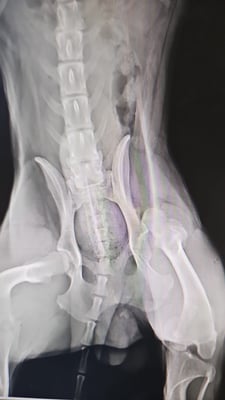

Am Mittwoch, den 28. Januar 2026, konnte Sebastian nun endlich operiert werden. Es wurde eine Femurkopfresektion durchgeführt, um ihm künftig ein möglichst schmerzfreies Leben zu ermöglichen und ihm die Chance zu geben, wieder besser laufen zu können. Zeitgleich wurde Sebastian kastriert.

On Wednesday, January 28, 2026, Sebastian was finally able to undergo surgery. A femoral head resection was performed to enable him to live as pain-free a life as possible and to give him the chance to walk better again. Sebastian was also neutered at the same time.